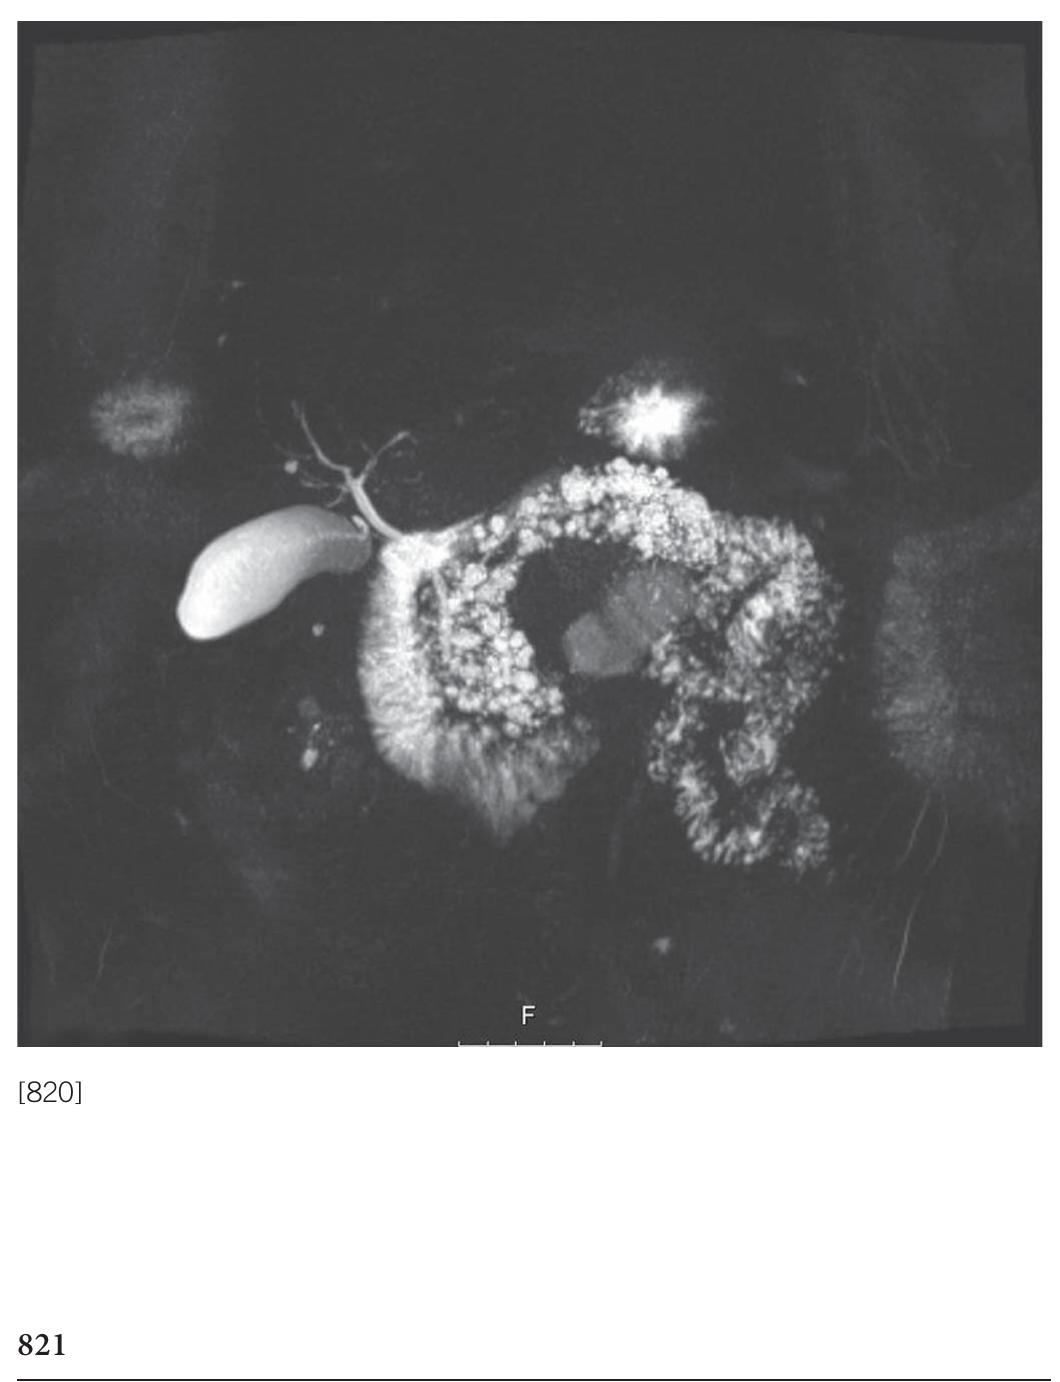

![[823] Polyp prolapsing into the second part of the duodenum; gross and endoscopic sonogram.](https://figures.academia-assets.com/72315061/figure_112.jpg)